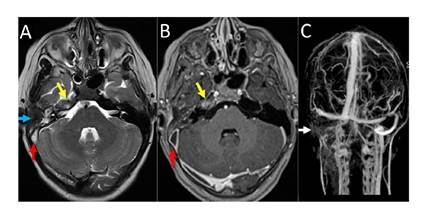

Los síntomas de hipertensión intracraneal persistían, por lo que en la Unidad de Neurocirugía Pediátrica se indicó administrarle acetazolamida (250 mg/día). Se practicó una resonancia magnética cerebral de 1,5 T en secuencias convencionales de forma simple y tras la administración de medio de contraste. Con este estudio se verificó una sinusitis crónica agudizada en ambos senos maxilares y etmoidales, y en el lado derecho, otomastoiditis aguda, apicitis petrosa, y trombosis de los senos sigmoides y transverso con extensión a la yugular interna; no había compromiso del seno cavernoso (figura 3).